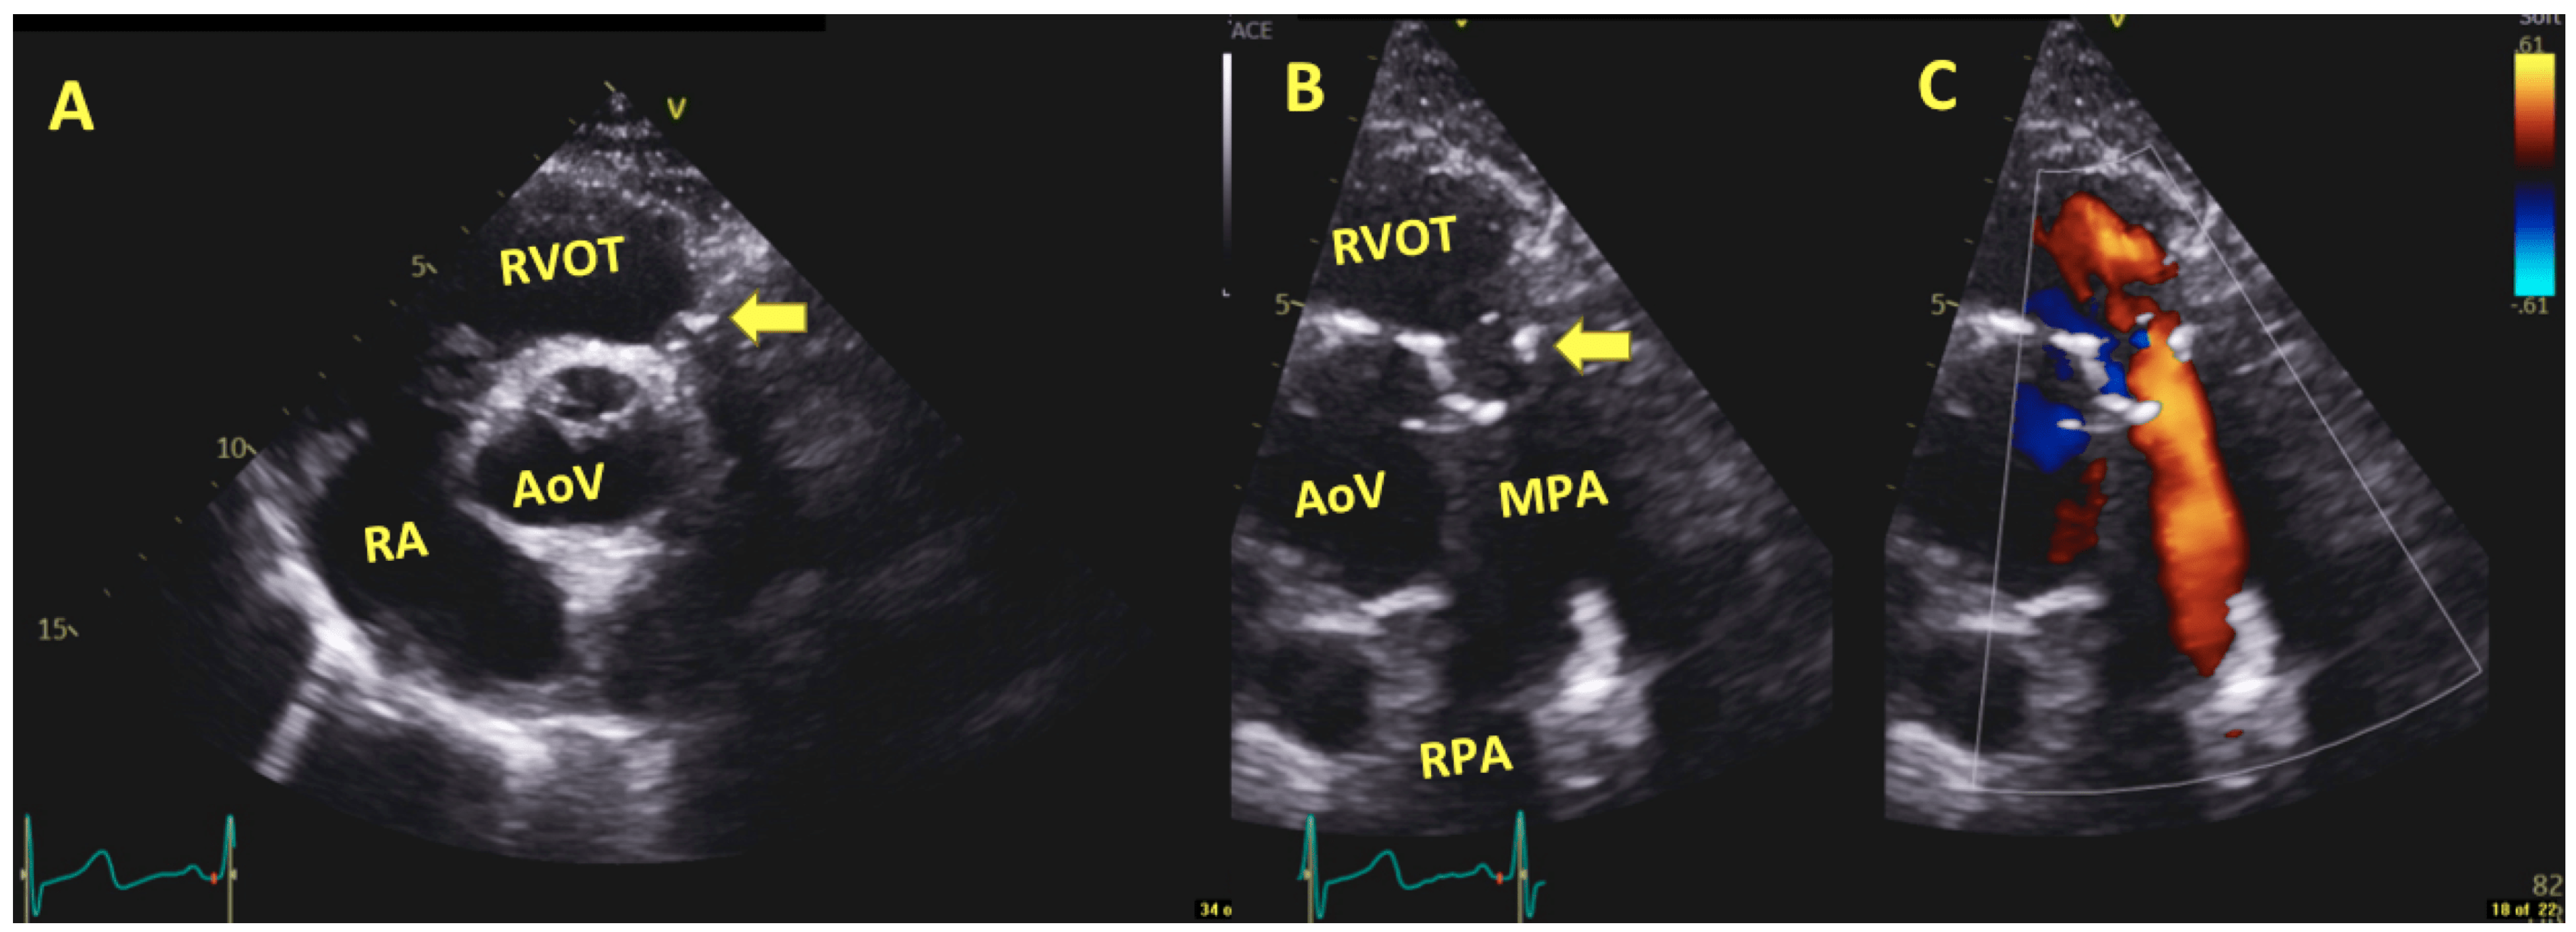

6.3. Post-Operative and Long-Term Follow-Up Imaging